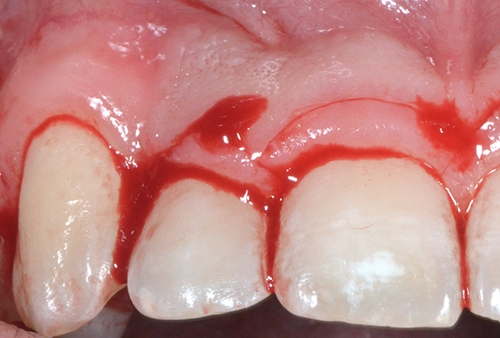

Diş tacının cərrahi uzadılması müxtəlif kliniki hallarda müxtəlif məqsədlərlə tətbiq edilən cərrahi müalicə prosedurudur. Bu metod estetik stomatologiyada “Gummy smile” (diş əti gülüşü) olaraq adlandırılan durumun ortadan qaldırılması məqsədilə geniş tətbiq olunur. Bu zaman kliniki hala bağlı olaraq bəzən yalnız diş əti, bəzən isə həm diş əti həm də sümükdən müəyyən miqdarda rezeksiya edilməklə (kəsilməklə) diş və diş ətinin estetik cəhətdən ideal görünüşü əldə olunur.

Bundan başqa, travma, ciddi karioz zədələnmə, normadan artıq preparasiya (diş yonulması) və s. nəticəsində diş tacının böyük ölçüdə dağılması zamanı bu dişlərin üzərinə qapaq, körpü konstruksiyalarının hazırlanması və ya bu dişlərin çıxan diş konstruksiyaları üçün (məsələn: teleskopprotezlər) fiksasiya elementi olaraq hazırlanması mümkün olmur. Buna səbəb diş toxumasının normadan artıq dağılmasıdır. Bu zaman tətbiq edilən metodlardan ən başlıcası diş tacının cərrahi uzadılmasıdır. Bu metodun tətbiqi ilə sümük müəyyən miqdarda uzaqlaşdırılaraq dişin tac hissesi uzadılmış olur. Nəticədə protetik olaraq yararsız diş yararlı duruma gətirilir.